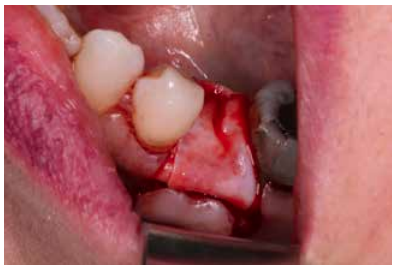

Materials and methods: A study was carried out on 6 patients from the Faculty of Dentistry of the Complutense University of Madrid performing the technique of alveolar ridge preservation. Two groups were established, a test group in which the alveolar socket was filled with calcium phosphate and added silicon and a control group where the socket was filled with bovine hydroxyapatite. After 3 months, a cone-beam computed tomography was performed to evaluate the bone density achieved by both biomaterials.

Andrés-Veiga et al,7 observed that this amount of bone resorption can vary between one individual and another and even in the same individual at different times of life, due to the influence of a series of local and systemic factors. Post-extraction alveolar ridge preservation (PAP) is a surgical technique aimed at reducing the collapse of the alveolar ridge after tooth extraction with a biomaterial, to facilitate subsequent implant rehabilitation8-10.